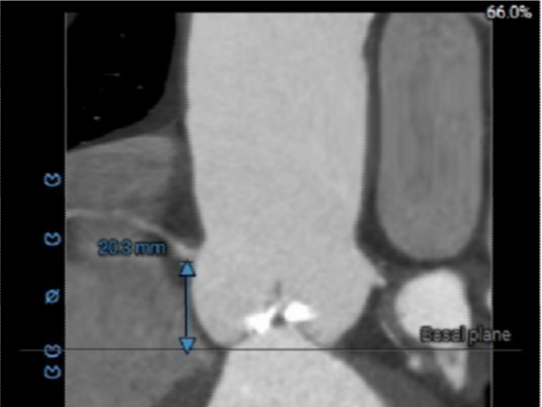

· 主动脉瓣环水平夹角51度,非横位心,主动脉弓宽度、角度尚可,弓部存在散在钙化;

虚拟瓣环与水平夹角

· 水平夹角51度,非横位心,主动脉弓宽度、角度尚可,弓部存在散在钙化,预估输送器过弓顺利,跨瓣难度增高,必要时采用Snare辅助。